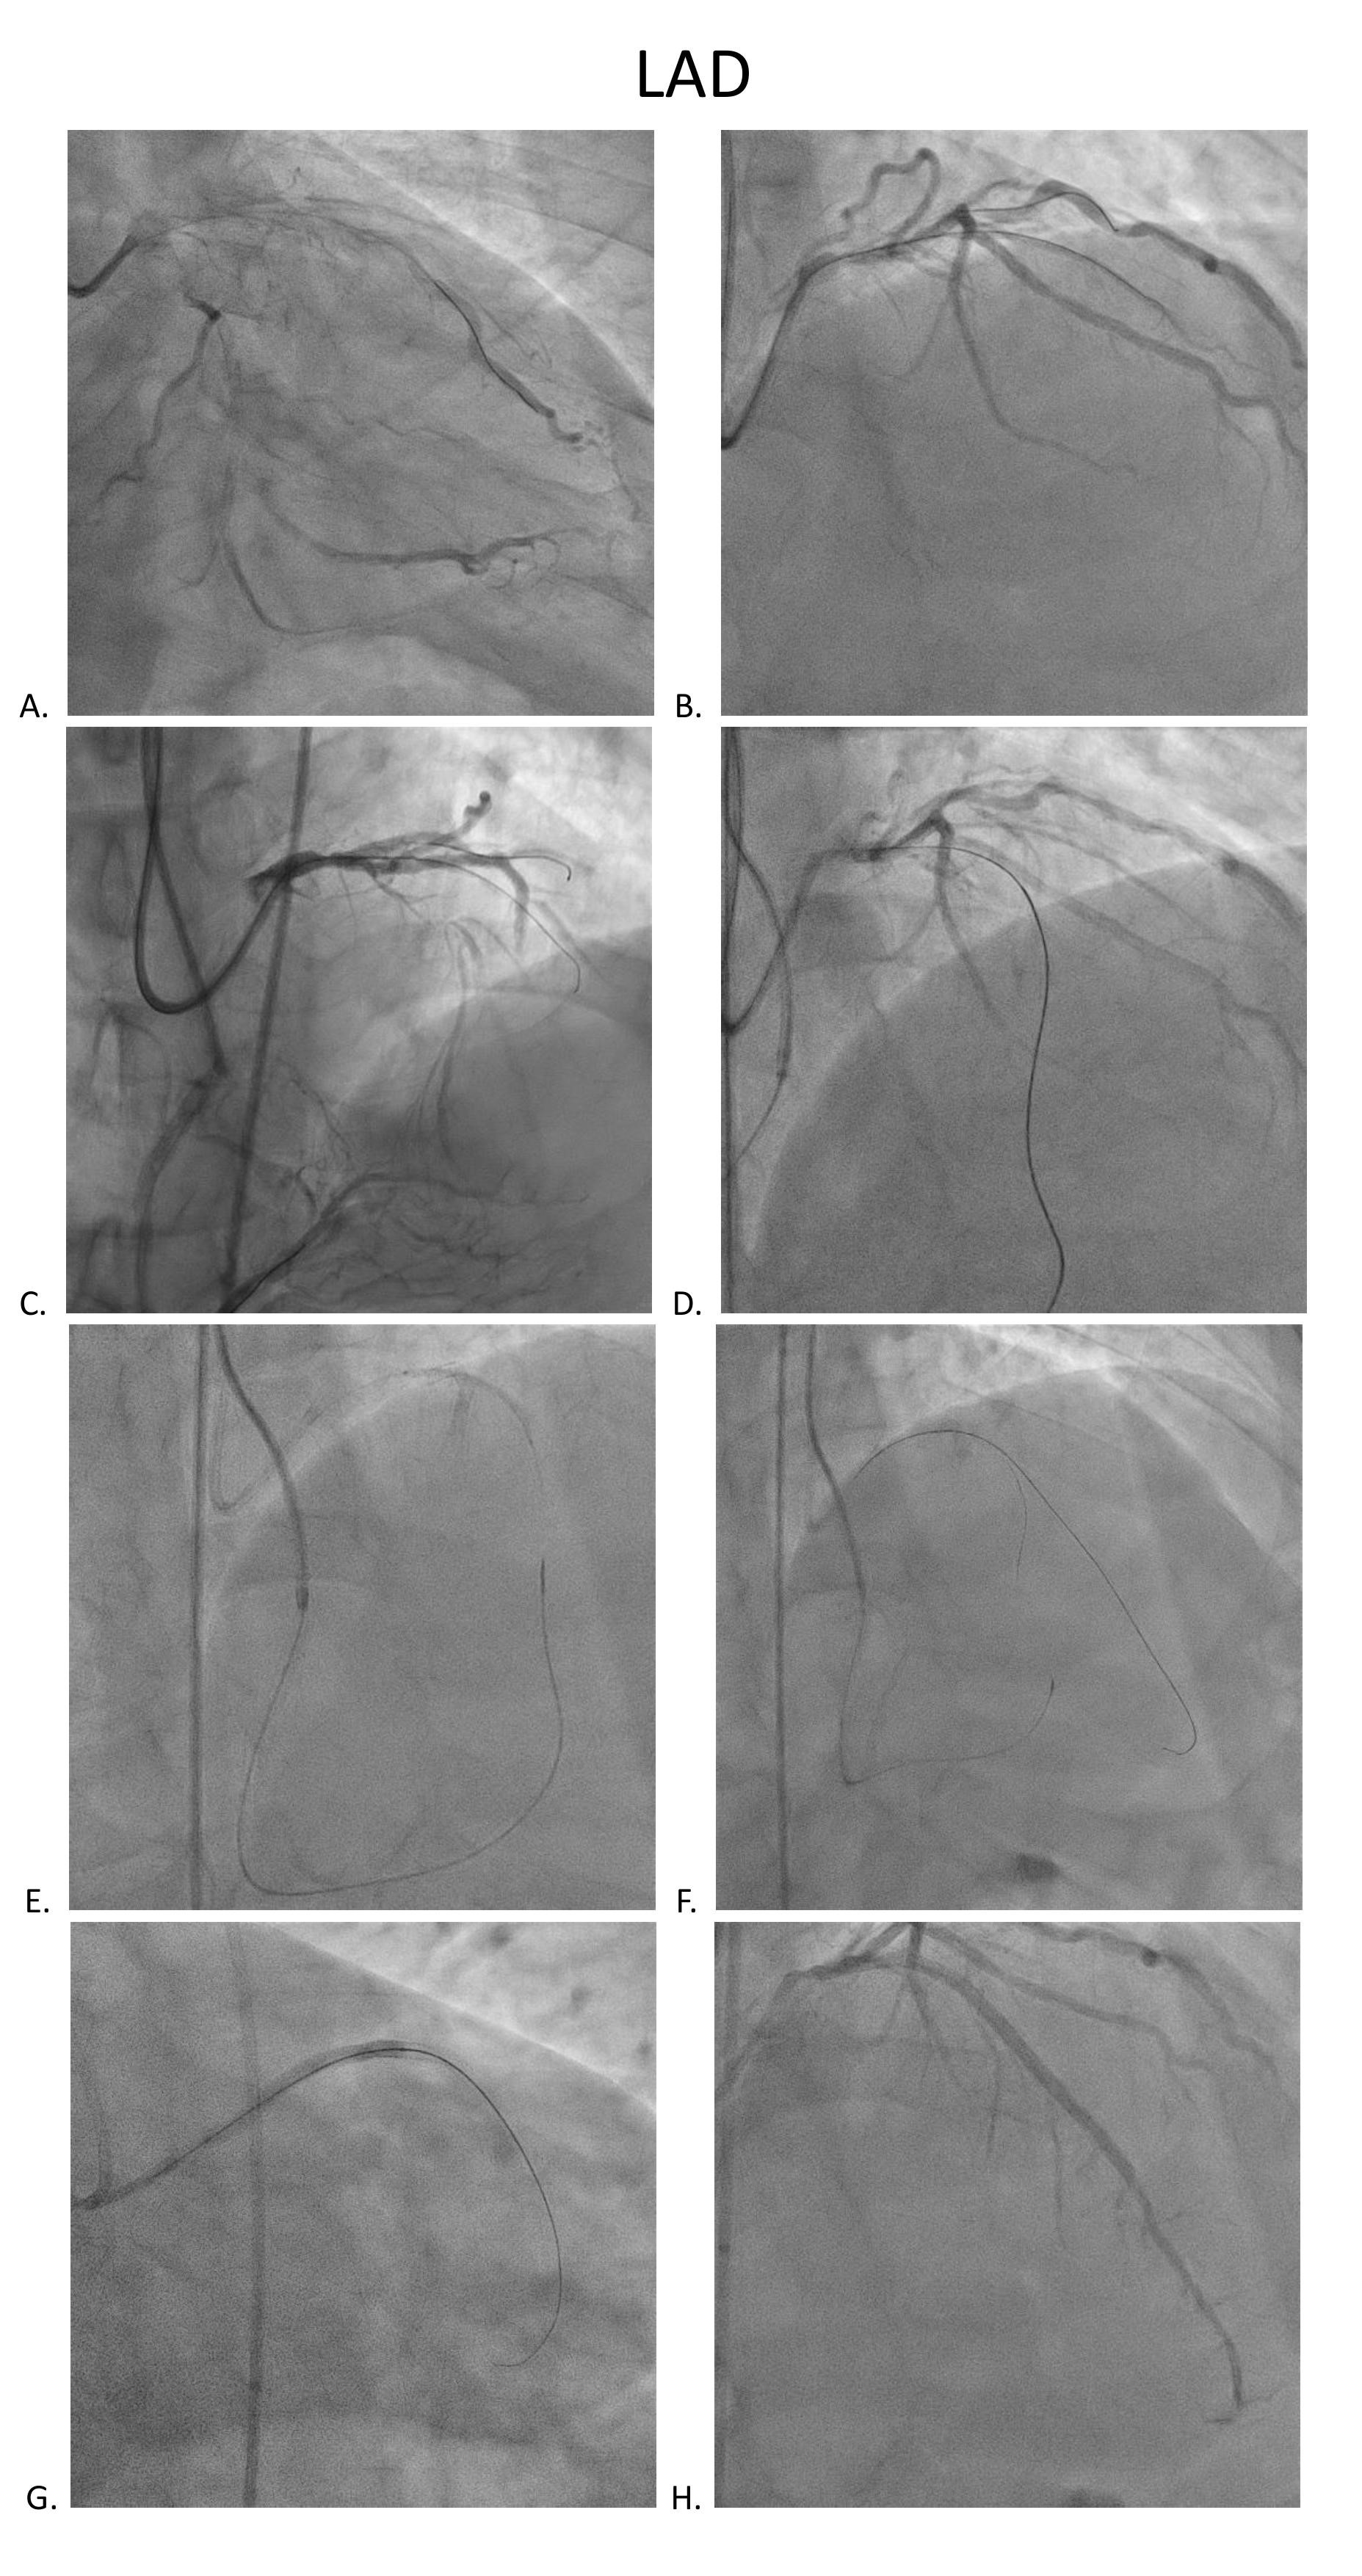

Coronary angiography disclosed orifice total occlusion with TIMI grade 0 antegrade flow at LAD, middle total occlusion at LCX, and RCA proximal total occlusion with auto-collateral to RCA distal.

Stage PCI for stumpless LAD-os-P CTO was arranged two months later. Antegrade strategy was tried initially, but shifted to retrograde approach due to wiring failed because of tiny LAD-M true lumen. We used SAL 1x6F guide via right femoral access. After trying, one septal collateral via PDA could be wired with a Fielder XT-R and Caravel. After switching the Caravel to Corsair Pro XS, it could be advanced to LAD-M. The CTO segment was retrogradely attempted with Conquest Pro, UB and finally reached LM body. Using a Sion blue, the wire could go into the antegrade guide, followed by advancing the Corsair Pro XS into the guide. The lesions were antegradely dilated with BC after RG 3 wire externalization and antegrade flow was established. By using a Crusade, the LAD proper could be successfully wired wtih a Fielder XT-A. LAD-M-D and LAD-os-P-M were predilated with a 2x30mm BC(IVUS confirmed all true lumen wiring) and respectively scaffolded with a 2.75x38mm Onyx and a 3x48mm Synergy. There was no residual stenosis over all 3 vessels.

Stage PCI for stumpless LAD-os-P CTO was arranged two months later. Antegrade strategy was tried initially, but shifted to retrograde approach due to wiring failed because of tiny LAD-M true lumen. We used SAL 1x6F guide via right femoral access. After trying, one septal collateral via PDA could be wired with a Fielder XT-R and Caravel. After switching the Caravel to Corsair Pro XS, it could be advanced to LAD-M. The CTO segment was retrogradely attempted with Conquest Pro, UB and finally reached LM body. Using a Sion blue, the wire could go into the antegrade guide, followed by advancing the Corsair Pro XS into the guide. The lesions were antegradely dilated with BC after RG 3 wire externalization and antegrade flow was established. By using a Crusade, the LAD proper could be successfully wired wtih a Fielder XT-A. LAD-M-D and LAD-os-P-M were predilated with a 2x30mm BC(IVUS confirmed all true lumen wiring) and respectively scaffolded with a 2.75x38mm Onyx and a 3x48mm Synergy. There was no residual stenosis over all 3 vessels.